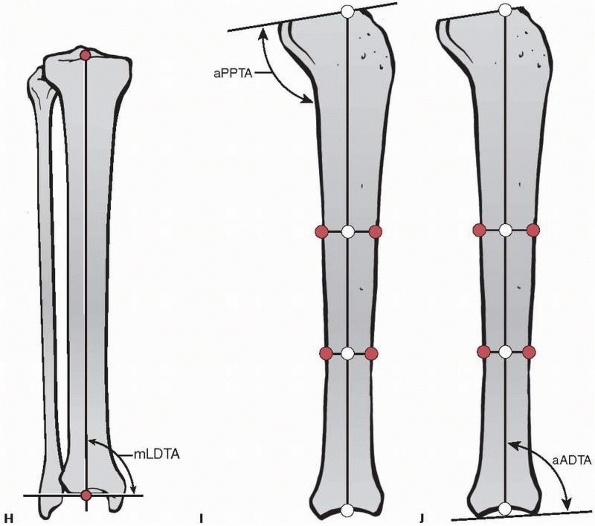

![]() |

FIGURE 26-7 Joint orientation angles. A. Anatomic medial proximal femoral angle. B. Mechanical lateral proximal femoral angle. C. Neck shaft angle. D. Anatomic lateral distal femoral angle. E. Mechanical lateral distal femoral angle. F. Anatomic posterior distal femoral angle. G. Mechanical medial proximal tibial angle. (continued)

FIGURE 26-7 (continued) H. Mechanical lateral distal tibial angle. I. Anatomic posterior proximal tibial angle. J. Anatomic anterior distal tibial angle.